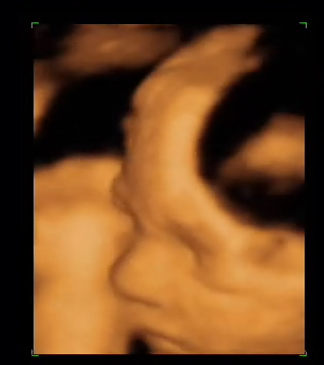

Es el mismo feto que el anterior y observen con que calidad se ven las piernas y pies. Es también un momento excelente para observar el sexo del feto.